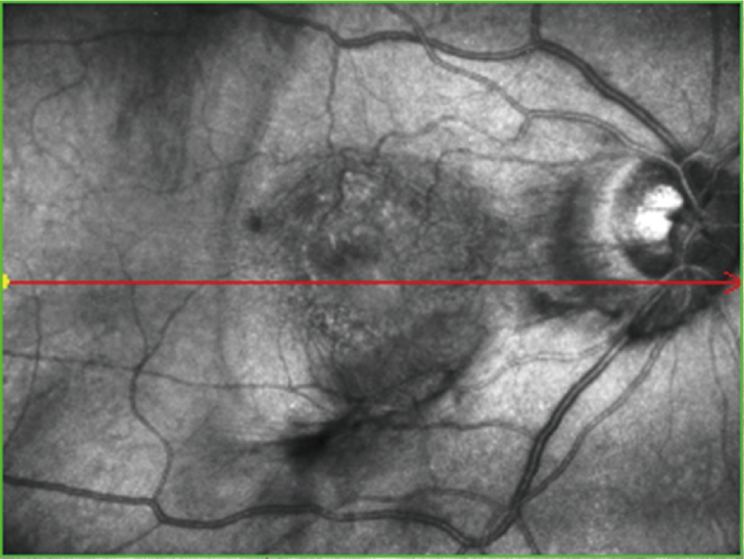

SLO イメージ & トレーシング HD plus